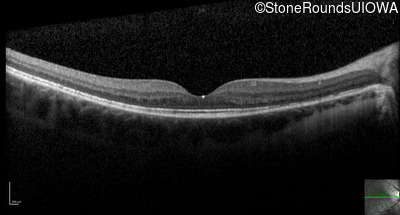

Optical Coherence Tomography - Right - 20/50 +2

Exemplar / OCT Stack